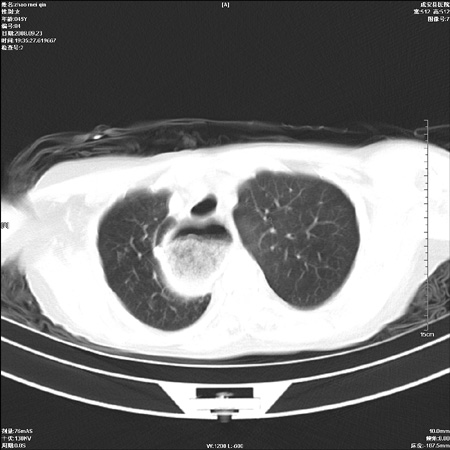

标题: CT15861:女 60 外伤后1小时 胸疼 [打印本页]

标题: CT15861:女 60 外伤后1小时 胸疼

外伤后1小时 胸疼 是外伤后引起的吗?

食道ca术后胸腔胃,右肺挫伤?

考虑术后改变(胸腔胃),建议询问病史.

非外伤性改变,典型的贲门失迟缓症

食道扩张明显下端逐渐变窄,大量食物存留,象贲门失迟缓症。